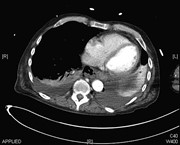

A large un-ruptured abdominal aortic aneurysm causing pulmonary embolism

Jahangir Sajjad and others

Journal of Surgical Case Reports, Volume 2015, Issue 7, July 2015, rjv092, https://doi.org/10.1093/jscr/rjv092